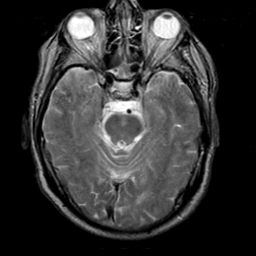

Meningioma, MR Study #2 -- Slice #6

[Home][Help][Clinical] Slice 6